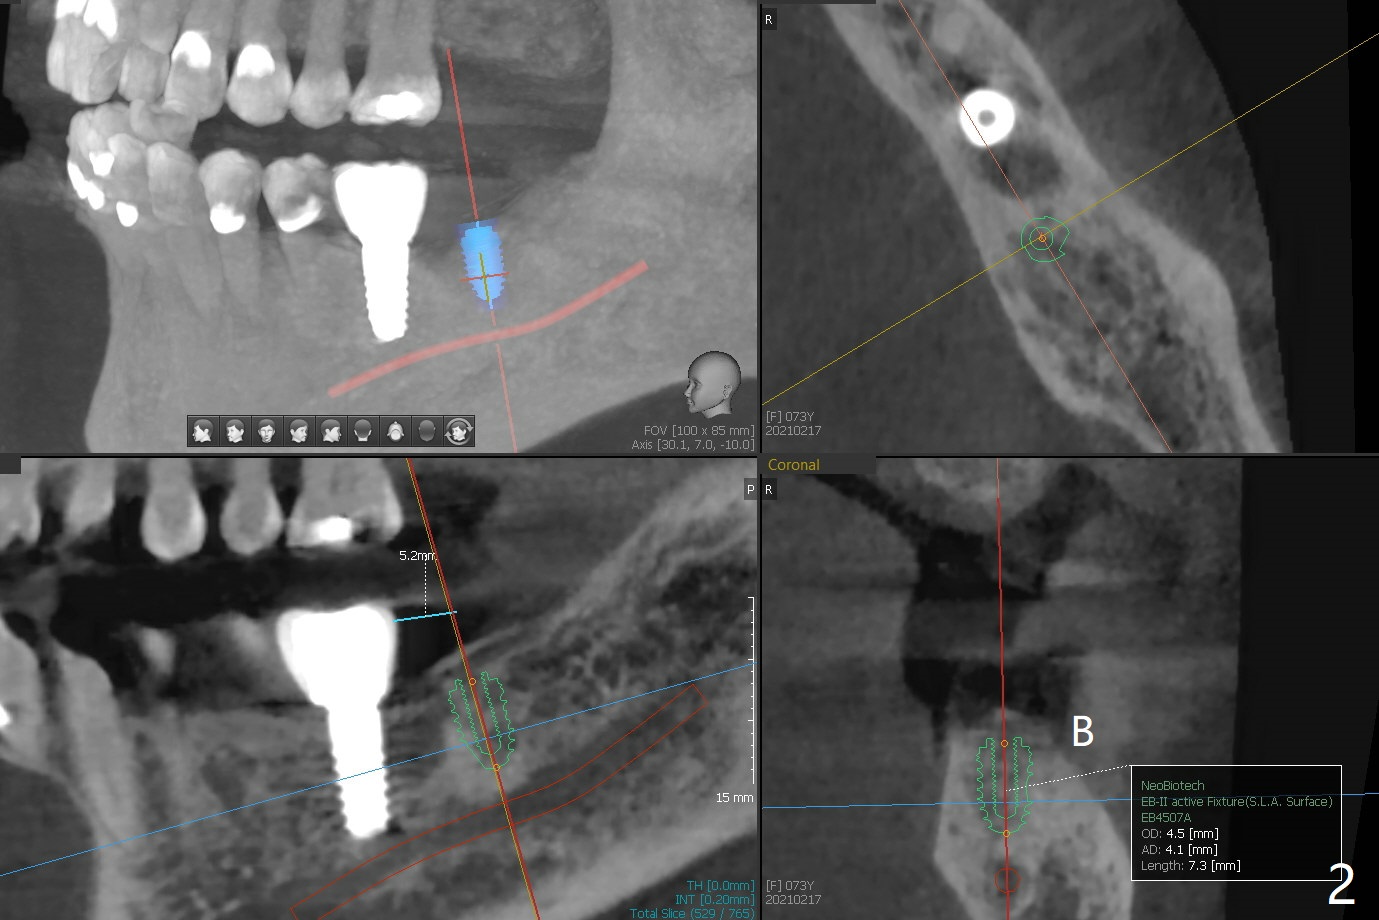

A 73-year-old woman with sign of occlusal wear breaks a lingual cusp of #31. After restoration, she agrees to have implants at #15 and 18 (Fig.1-3).